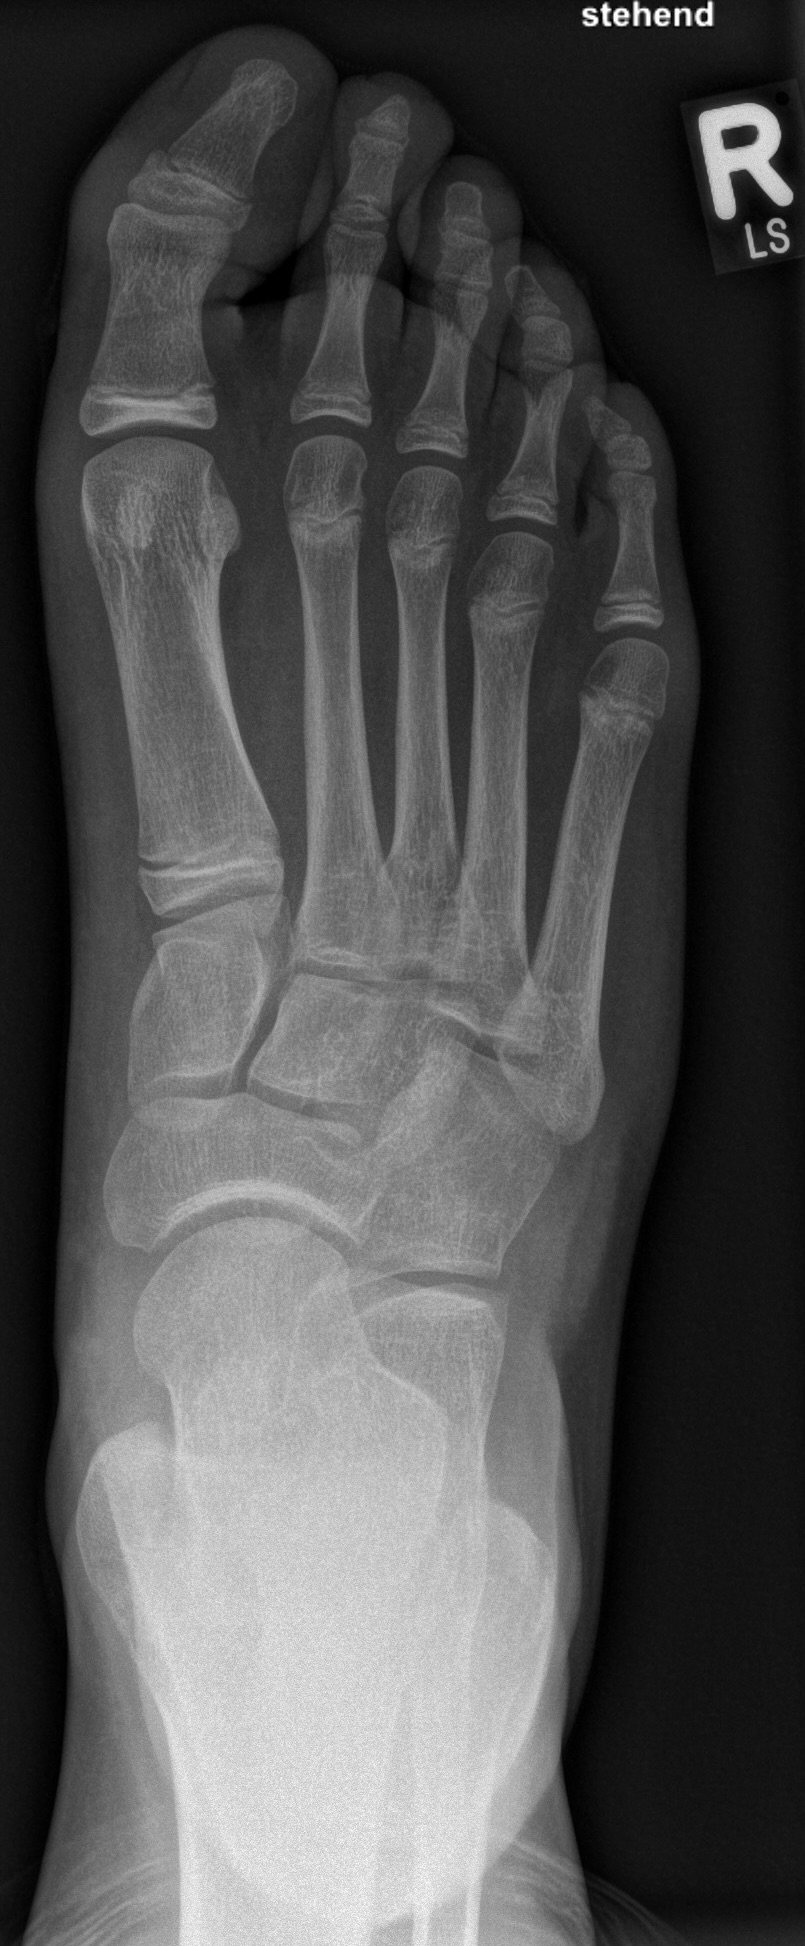

Die Chevron Osteotomie 1 ist ohne Komplikationen am wachsenden Skelett durchführbar. Das Metatarsale I besitzt distal keine Wachstumsfuge, die geschädigt werden könnte. Die „französische Methode nach Marc Elkaim“ eignet sich für Kinder ganz besonders (Abb. 28).

Abb. 28 a-g: Radiologischer Verlauf einer Chevronosteotomie nach dem Verfahren von M. Elkaim mit prä- (a-c drei unterschiedliche Ansichten) und intraoperativen Röntgenbildern in zwei Ansichten (d-e) sowie postoperativ zwei Ansichten (f-g).

Zum Lesen der Bildbeschreibung und zur Vollansicht bitte die Bilder anklicken. Bilder: A. Helmers.

Sie wird über eine eigene Tapetechnik fixiert und kann bei einem erhöhten Intermetatarsale-Winkel alternativ zur Scarf-Osteotomie durchgeführt werden. Nachteile der Methode sind eine deutliche Verkürzung durch die Fräse sowie eine starke Plantarisierung des Metatarsale I Köpfchens. Um die Verkürzung zu vermeiden, wird verlängernd in Richtung des Metatarsale II Köpfchens (nicht wie offen in Richtung Metatarsale IV Köpfchen) osteotomiert. Gleiches gilt für die starke Plantarisierung, die durch den Knochenverlust der Fräse entsteht. Die Korrektur eines kindlichen oder jugendlichen Hallux valgus ist mit der Methode ansonsten suffizient durchführbar. Wird verkürzt, muss ausreichend plantarisiert werden, um eine Transfer-Destabilisierung MT II-IV zu vermeiden.